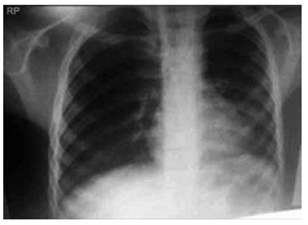

Paciente de 67 anos, tabagista 40 maços/ano, ex- -fumante há 3 anos, diagnosticado com doença pulmonar obstrutiva crônica (DPOC), classificado como GOLD D há 4 anos (VEF₁: 38% do previsto). Faz uso de tiotrópio e formoterol regularmente, sem oxigenoterapia domiciliar. Chega ao pronto atendimento com dispneia intensa e aumento de volume de escarro purulento há 3 dias, evoluindo com cansaço progressivo e confusão mental nas últimas horas.

Ao exame físico: FR: 28 irpm, uso de musculatura acessória SatO₂: 82% em ar ambiente. PA: 138 × 86 mmHg; FC: 112 bpm; T: 37,8 °C.

Ausculta pulmonar com roncos difusos e sibilos esparsos.

Gasometria arterial pH: 7,28; PaCO₂: 68 mmHg; PaO₂: 54 mmHg; HCO₃⁻: 31 mEq/L.

Radiografia de tórax a seguir: